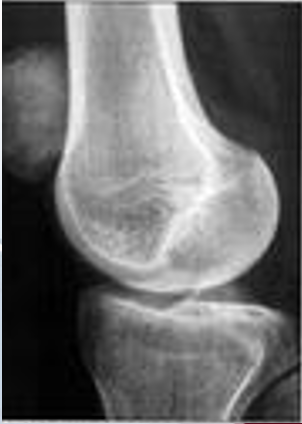

带线锚钉在膝关节的应用

应用范围:

• 侧副韧带的修复

• 交叉韧带止点撕脱骨折的修复

• 髌骨不稳等

1.带线锚钉治疗侧副韧带止点断裂

膝关节内侧副韧带(medial collateral ligaments,MCL)是膝关节内侧的主要稳定结构,膝关节外侧暴力常常导致其损伤。